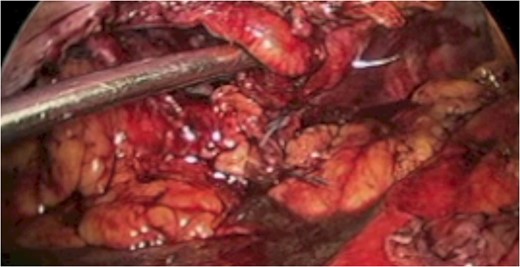

A 43-year-old male patient presented with a right-sided traumatic lumbar hernia after a blunt mechanism. The patient had been pinned between a dirt-mover’s claw arm resulting in a crush mechanism. He sustained injuries to the lumbar spine, sacrum, abdominal wall and 12th rib. On presentation, he did not have clinical or radiographic evidence necessitating abdominal exploration and was observed in a monitored setting. Computed tomography imaging demonstrated a Grynfeltt defect with herniation of the ascending colon and cecum through an area defined by the 12th rib, quadratus lumborum and internal oblique (Figures 1 and 2). After several days of observation and recuperation, the patient continued to have significant pain overlying the hernia site. We electively brought him to the operating room on post-injury Day 4. A laparoscopic repair of the traumatic hernia was performed. Key operative steps included: (i) Wide exposure of the hernia defect via incision of the peritoneum and transversalis as well as mobilization of the ascending colon and duodenal sweep (Figures 3 and 4). (ii) Primary repair of the defect with intra-corporeal suturing of the oblique musculature (Figures 5 and 6). (iii) Placement of an underlay mesh with appropriate redundancy at least 4 cm in all directions around the defect and seating against the iliac crest (Figure 7). Post-operative imaging demonstrates obliteration of the hernia defect and restoration of the abdominal wall (Figures 8 and 9). The patient has recovered, returned to the work force and has no pain or bulge at the repair site 6 months after injury.

Step 1 begins with incision of the peritoneum overlying the hernia.